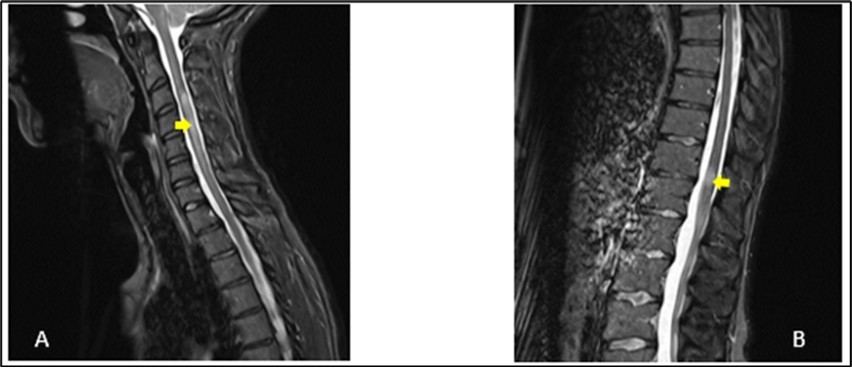

Figure 2.Sagittal T2-weighted spine MRI showing at cervical level (A), a spontaneous hyperintense lesion of 5 cm from C3 to C6 and at thoracic level (B), a spontaneous hyperintense lesion of 1.5 cm from T11-T12

A 27-year-old girl presented at the emergency department, at a hospital in the Paris region on March 9, 2020 with complaints of left interscapular pain, paresthesias and weakness in the ipsilateral upper limb. These symptoms followed paresthesias on the fingertips of her right hand the day before her admission. She did not report fever, sphincter disorder or gait disturbance. No eye symptoms reported. In her medical history, she was treated two weeks earlier for pneumonia with COVID-19. There was no another previous infectious episode apart from the COVID-19. She had no history of diabetes, hypertension, cerebrovascular disease or migraine. She had not history of multiple sclerosis or Neuromyelitis Optica Spectrum Disorder (NMOSD). There was no history of smoking, contraception drugs intake or any prolonged drug intake. On the first examination in the neurology department where she was transferred on the same day of her admission, she had good general condition and was apyretic. She had a pulse rate of 74/min and the blood pressure was at 130/80 mmHg. The neurological evaluation showed on the left side, a muscular weakness grade 4 in the proximal part and grade 3 in the distal part of upper limb, and in the lower limb, the weakness graded at 3 in the distal part, using the Medical Research Council Scale (MRC) for muscle strength. There was no weakness on the right side. Deep tendon reflexes in both left and right were normal. Babinski sign was found on the left side. She presented tactil and algic hypoesthesia in the lower left limb ascending until the C4 level in the left side. There was no perineal sensitive trouble. The remain neurological exam including, higher functions, cranial nerves, was with no particularity. Otherwise, cardiovascular and respiratory systems examination were within normal limits. Blood laboratory tests were within the normal ranges, including complete blood count (CBC), C-Reactive protein, renal and liver functions and blood serum ionogram. Human Immunodeficiency Virus (HIV) tests including p24 antigen and antibodies to HIV were negative. Syphilis serology and Aquaporin 4 antibody were also negative. Encephalic Magnetic Resonance Imaging (MRI) demonstrated scattered hyperintense lesions on FLAIR imaging in deep hemispheric and juxtacortical white matter in supratentorial and in infratentorial floors (Figure 1). Medullary MRI showed T2 hyperintense lesions in left cervical hemi-marrow extending from C3 to C6, at T3, T4, T11 and T12 levels (Figure 2). These lesions were not enhanced after injection of gadolinium. The Cerebrospinal fluid (CSF) appeared to be colorless and clear with no cell detected microscopically; cerebrospinal protein level, 0.4 mg/L, glucose (Glu) level, 3.2 mmol/L; and instant blood glucose level, 5.2 mmol/L. CSF bacterial culture demonstrated no growth after 3 days, and herpes simplex virus 1 and 2, varicella-zoster virus test was negative. Reverse transcription-polymerase chain reaction (RT-PCR) assay test for COVID-19 was negative in the CSF. The final diagnosis was an ADEM secondary to novel coronavirus (nCov) infection. She was given methylprednisolone (1000 mg IV per day for 5 days) followed by Intravenous Immunoglobulin (IVIG) therapy at 0.4 g/kg daily for 5 days. Together with chemotherapy, she received physiotherapy coupled with occupational therapy. The outcome was good with improvement of weakness and paresthesias. There was residual tingling on the fingertips of the left hand. The patient was discharge on day 13.